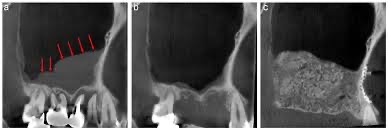

需先清創、讓骨頭恢復癒合數月後,重新評估齒槽骨狀況再進行植牙或合併其他術式(如:鼻竇頂骨補骨手術、鼻竇開窗齒槽骨重建手術、自體齒槽骨重建手術…等),成功率才會高。